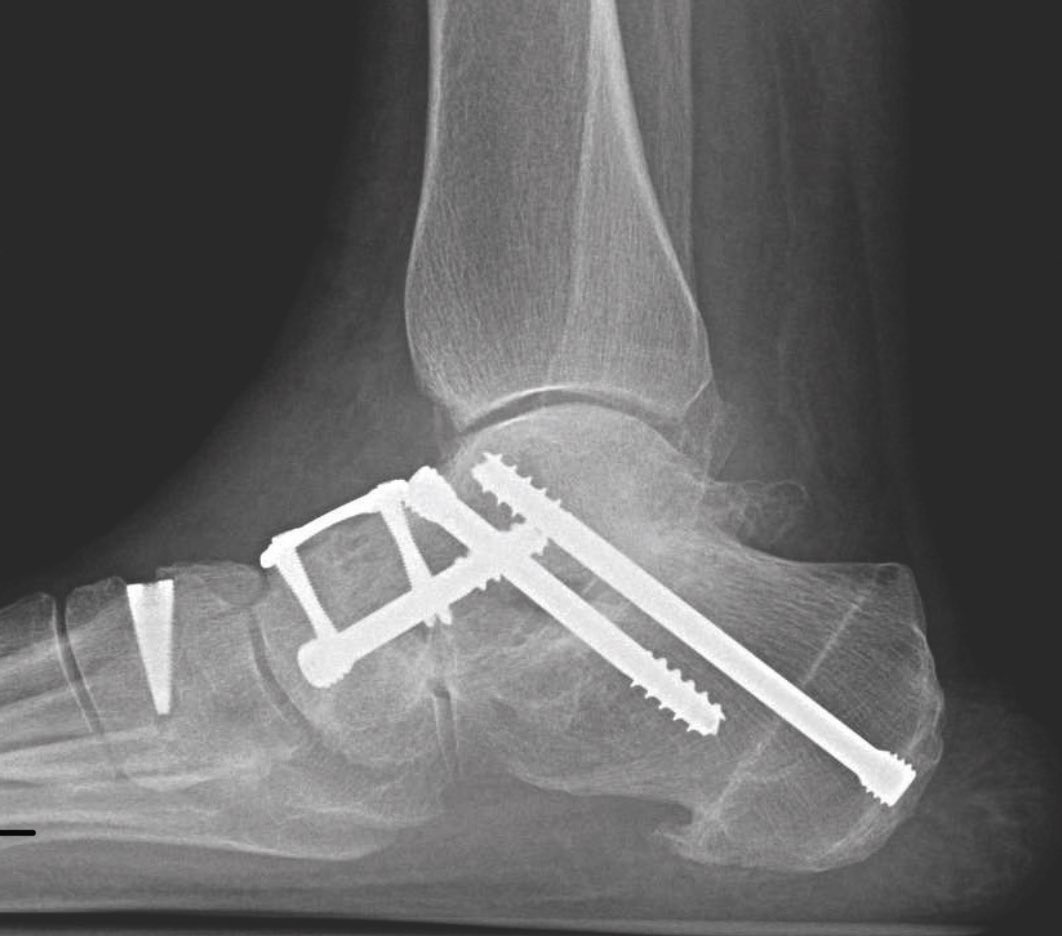

- التدخل الجراحي لتسطح القدم بشكل عام يكون عن طريق :

١. إعادة إصلاح استقامة العظم بتعديله بمسامير أو غيرها

٢. نقل أو استطاله الأوتار

٣. اصلاح الأربطة المتمزقة والممتدة

- التدخل الجراحي في الحالات المتقدمة من تسطح القدم يكون عن طريق تعديل و تثبيت مفاصل مؤخرة القدم أو منتصف القدم حسب الحالة بحيث لا تؤثر بشكل واضح على المشي أو الحركة